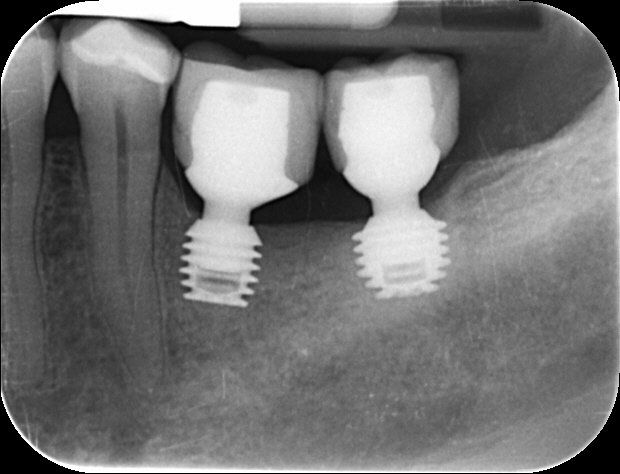

A bridge

- involves three or four teeth over two implants and again is made of high strength natural shade white material.